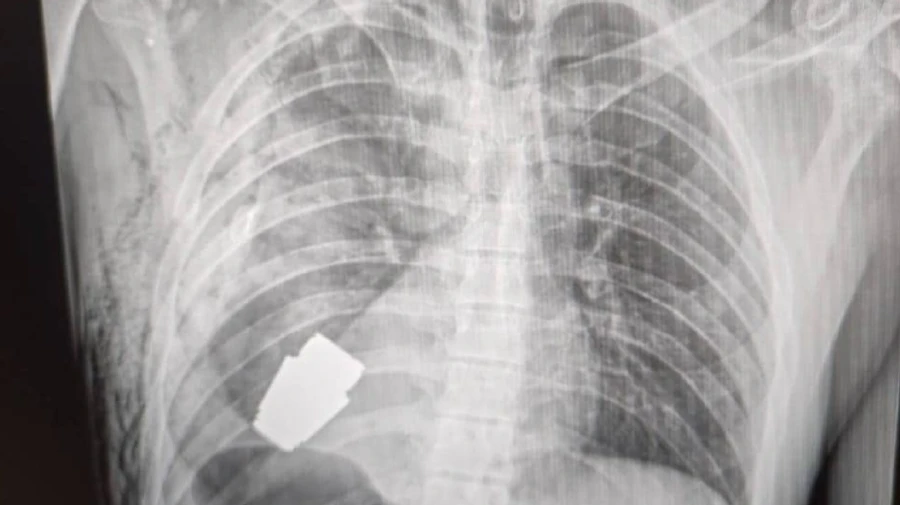

Українські лікарі під наглядом саперів провели унікальну операцію: видалили гранату ВОГ, що не розірвалася, з тіла військового.

Пряма мова: "Не кожне поранення в області серця є смертельним! Військові лікарі провели операцію з видалення гранати ВОГ, яка не розірвалася, з тіла військовослужбовця.

Її було видалено у присутності двох саперів, які страхували безпеку медичного персоналу.

Операція проводилася одним з найдосвідченіших хірургів ЗСУ - Андрієм Вербою, без електрокоагуляції, оскільки граната могла детонувати у будь-який момент".